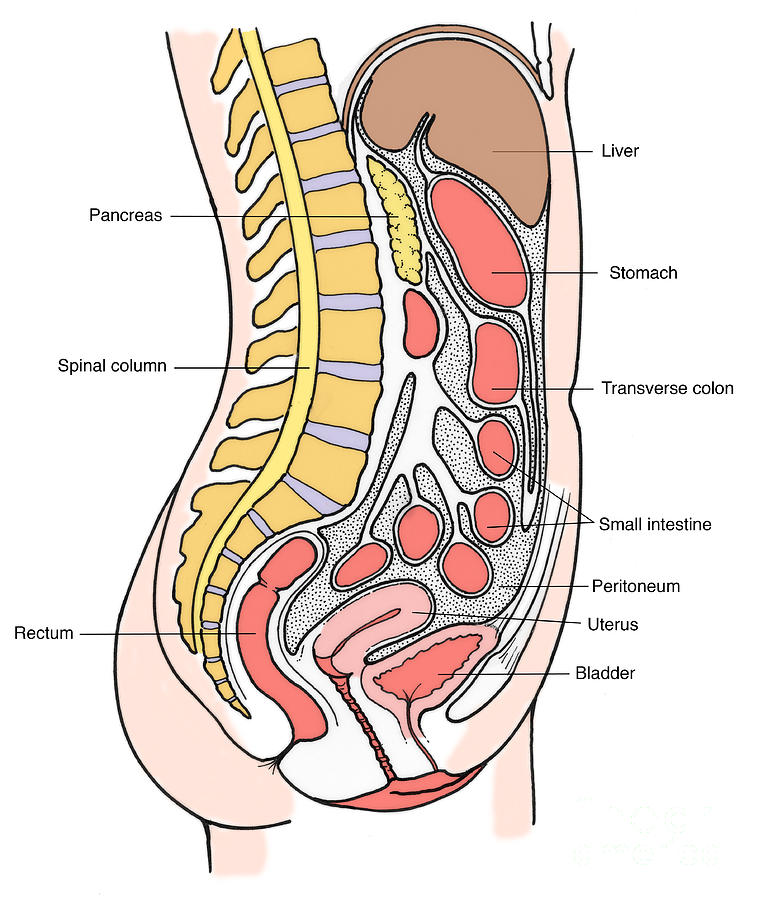

Female Abdominal Anatomy Images . Female Abdominal Anatomy Images …

Female Lower Back Anatomy Internal Organs : Bones of the Pelvis and …

Female Abdominal Anatomy Pictures – koibana.info | Anatomy organs …

Section Of Female Pelvic Organs Stock Photo – Download Image Now …

Abdominal and Pelvic Pain in the Nonpregnant Female | Tintinalli’s …

Stock Female Pelvis: Normal Anatomy — Illustrated Verdict

Female Abdominal Pain | Types | Symptoms | Causes | Diagnosis | Treatment